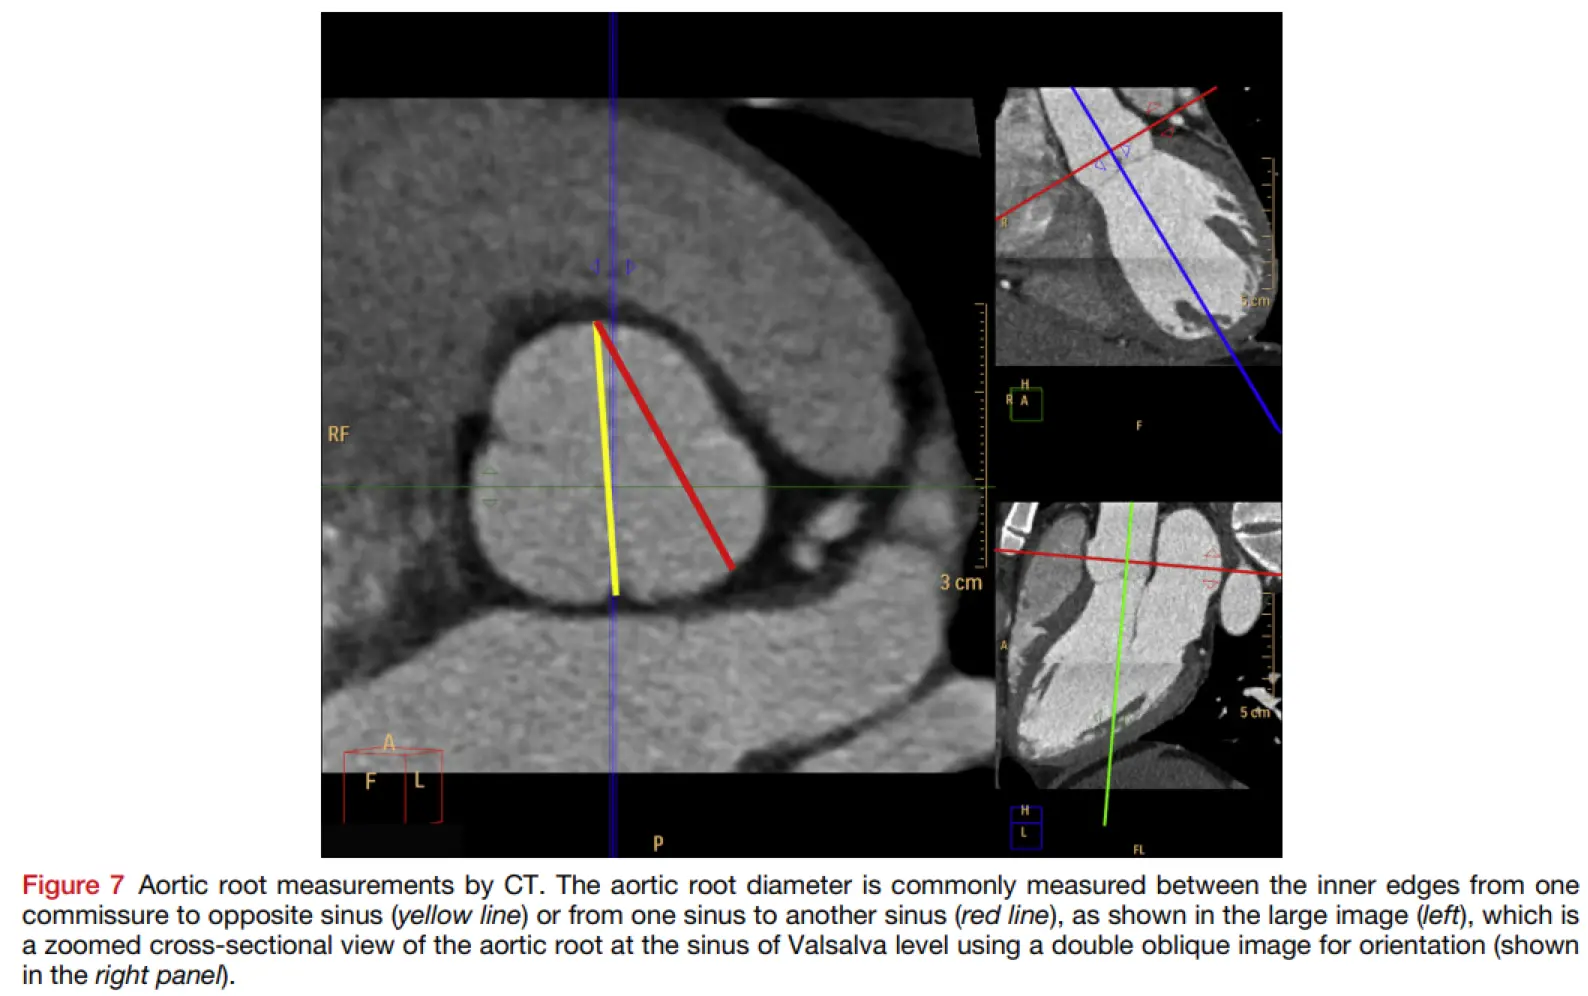

Methods for measuring the aortic valve on CT include 1

- commissure-to-cusp

- cusp-to-cusp

- Iyer mentioned that cusp-to-cusp is more consistent and in-line with Echo measurements